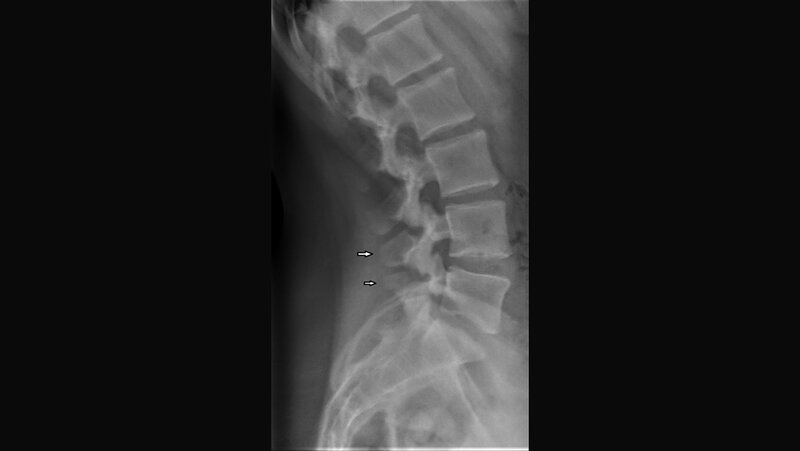

Anomalien und Normvarianten – Skelettale Veränderungen 3.35: Wirbelfortsatzdysplasien

Neben der Hypoplasie des Wirbelbogens können, nicht obligatorisch, Hypo- und Dysplasie der Wirbel- und Gelenkfortsätze, Elongation der Zwischenwirbelgelenkstücke und Spondylolysen auftreten. Die kongenitale Natur der Veränderungen ist erblich möglich.

Besides hypoplasia of the vertebral arch may occur, but not compulsory, hypoplasia and dysplasia of vertebral and articular processes, elongation of the bone situated between the joints and spondylolysis. The congenital nature of this changes is not proved, but heredity seems probable.